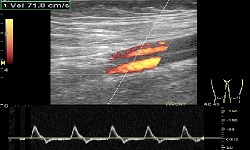

Doppler żył-prawidłowe przepływy.